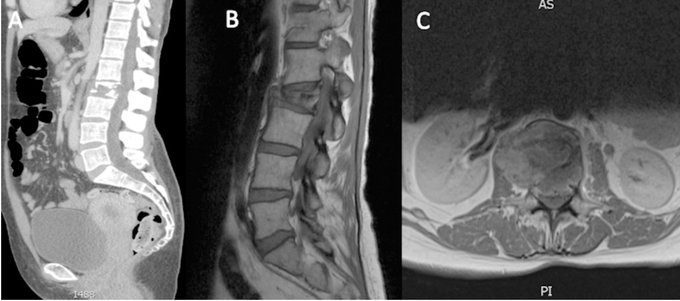

La reconstrucción de la columna después de una espondilectomía en bloque es un desafío y puede requerir una intervención multidisciplinaria. La resección en bloque del tumor de la columna con embolización de los vasos receptores locales para el control del tumor limita las opciones reconstructivas. A continuación, describimos un caso en el que los esfuerzos combinados de los equipos de cirugía ortopédica, general y plástica permitieron la reconstrucción exitosa de un defecto vertebral lumbar multinivel.

Un colgajo libre de peroné dentro de una estructura de caja de titanio anastomosada a los vasos gastroepiploicos izquierdos mediante un colgajo de flujo continuo omental pediculado es un método viable y novedoso para la reconstrucción de un defecto vertebral multinivel.